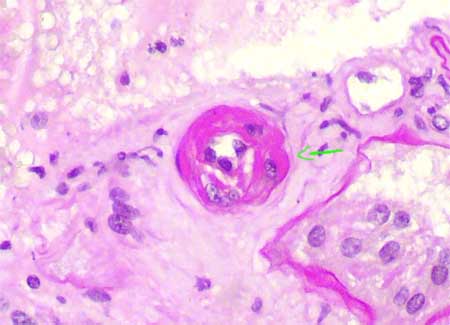

Lesiones arteriales de rechazo crónico: Consisten en proliferación fibrosa de la íntima con células inflamatoria mononucleares en ella: principalmente linfocitos, monocitos e histiocitos vacuolados; hay disrupción de la íntima, mejor apreciada con tinciones para elástico. Encontraremos también proliferación de células miointimales y formación de una segunda "neoíntima". De todos estos hallazgos el más sugerente de rechazo es la presencia de células inflamatorias en la íntima fibrótica.

Figura 16. En el rechazo crónico hay fibrosis intimal acompañada de células inflamatorias mononucleadas e histiocitos espumosos (en algunos casos) (flechas). Hay fragmentación de la lámina elástica interna y disminución de la luz arterial. (H&E, X300).